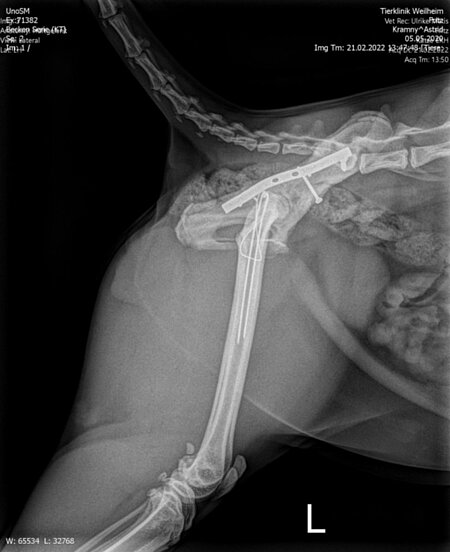

Zuerst wurden das ausgerenkte rechte Kreuz-Darmbein-Gelenk sowie der in seiner unmittelbaren Nachbarschaft verlaufende Ischias dargestellt und das Darmbein nach seiner Reposition mit einer 2,0 mm dicken und 24 mm langen Schraube an den Kreuzbeinkörper fixiert. Nach dem Wundverschluss wurde der Kater auf die andere Körperseite gelagert und sodann der direkt vor der Hüftgelenkspfanne Eine weitere Schraube diente der Adaptation eines Darmbeinsplitters an die Hauptfragmente. Da die Freilegung dieser Beckenregion meistens auch einen Knochenschnitt am Oberschenkel zum Verlagern der Kruppenmuskeln erfordert, wurden die Endsehnen dieser Muskeln mit dem knöchernen Segment abschließend durch 2 Bohrdrähte und einer 8-förmigen Drahtschlinge wiederbefestigt.

Röntgenbilder mit freundlicher Genehmigung Tierklinik Weilheim.

Bei der Nachuntersuchung des Patienten sechs Monate später präsentierte sich der Kater völlig beschwerdefrei und war sowohl in der Beckenregion als auch an den Gliedmaßen kräftig bemuskelt. Die Knochenbrüche waren sehr gut geheilt, ohne Einengung der Beckenhöhle und ohne die Ausbildung einer Hüftgelenksarthrose. Von einer Entfernung der Implantate wurde abgesehen, da alle Metallteile reizlos und ohne Lageveränderung integriert waren.